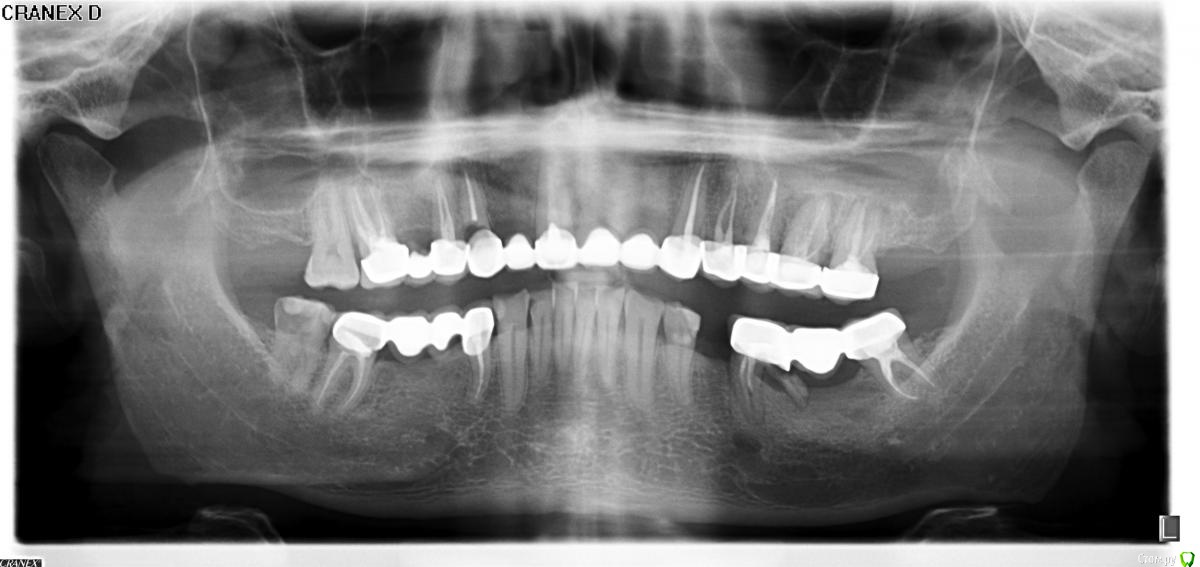

Капитальный ремонт мостов. Вопросы по удалениям-лечению.

13- кариес корня, недопломб верхушк 3мм, пустоты в канале

26, 27 - кеста 4-5 мм

36,

48

все приговорили удалять!

16, 17 - лечить

Какие будут мнения? В основном интересуют 26, 27.